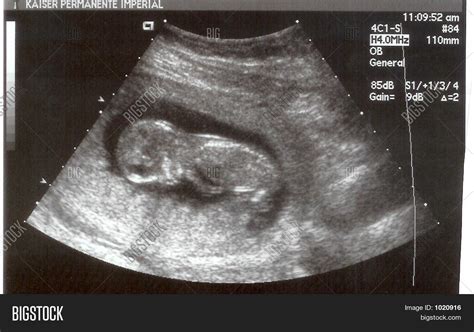

Pregnancy is an exciting journey filled with milestones, and one of the most anticipated moments is the 14 week sonogram. This ultrasound scan provides valuable insights into the development of the fetus and offers parents a glimpse into their baby's world. Understanding what to expect during a 14 week sonogram can help alleviate anxiety and enhance the overall experience.

A 14 week sonogram is an ultrasound examination performed around the 14th week of pregnancy. It is typically part of the routine prenatal care and is often referred to as the “nuchal translucency scan.” This scan is crucial for assessing the baby’s development and detecting any potential abnormalities.

What to Expect During a 14 Week Sonogram

During a 14 week sonogram, the procedure is generally straightforward and painless. Here’s what you can expect:

• You will be asked to lie down on an examination table.

• A gel will be applied to your abdomen to enhance the ultrasound images.

• The sonographer will use a transducer to capture images of the fetus.

• The procedure typically takes about 20-30 minutes.

Some women may experience discomfort from the pressure of the transducer, but it is generally well-tolerated.